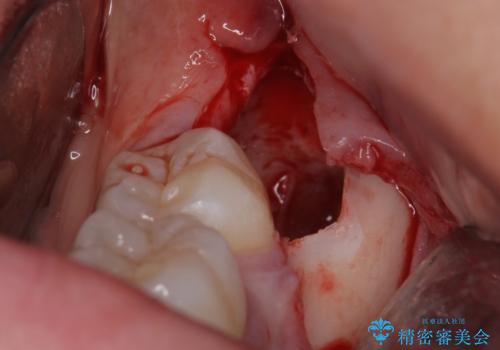

- 親知らずの抜歯希望で来院されました。

左側の親知らずを上下同時に抜いていきます。

時間は約60分で施術しました。